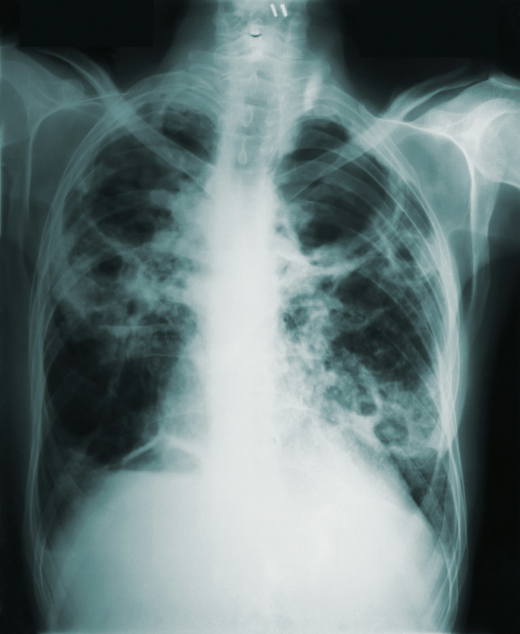

• radiographie

Radiologie

Radiographie standard numérique

Examen rapide et précis pour l’analyse des structures osseuses et pulmonaires.